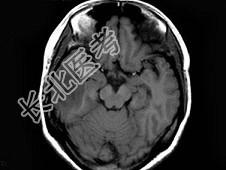

- 单项选择题女,25岁, 头痛3个月,头颅MRI平扫及增强扫描如图, 最可能的诊断是 ( )